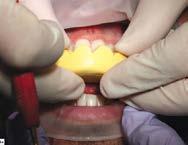

Ridgfield Park, N.J.) o TuffTemp™ Plus (PULPDENT; Watertown, Mass.), rellené la matriz putty y cemento sobre las piezas 22-12 sin preparar. Removí el exceso de acrílico mientras el material se asentaba en la boca del paciente para reducir el tiempo que hubiera necesitado para limpiar el acrílico endurecido (Figura 5).

La matriz fue removida después de que el material del mockup se asen tó. Se pueden realizar pequeños ajus tes en este punto de ser necesario. El mockup intraoral nos dio la oportu nidad, tanto a mí como a mi pacien te, de revisar la estética, fonética y el funcionamiento general del diseño (Figura 6).